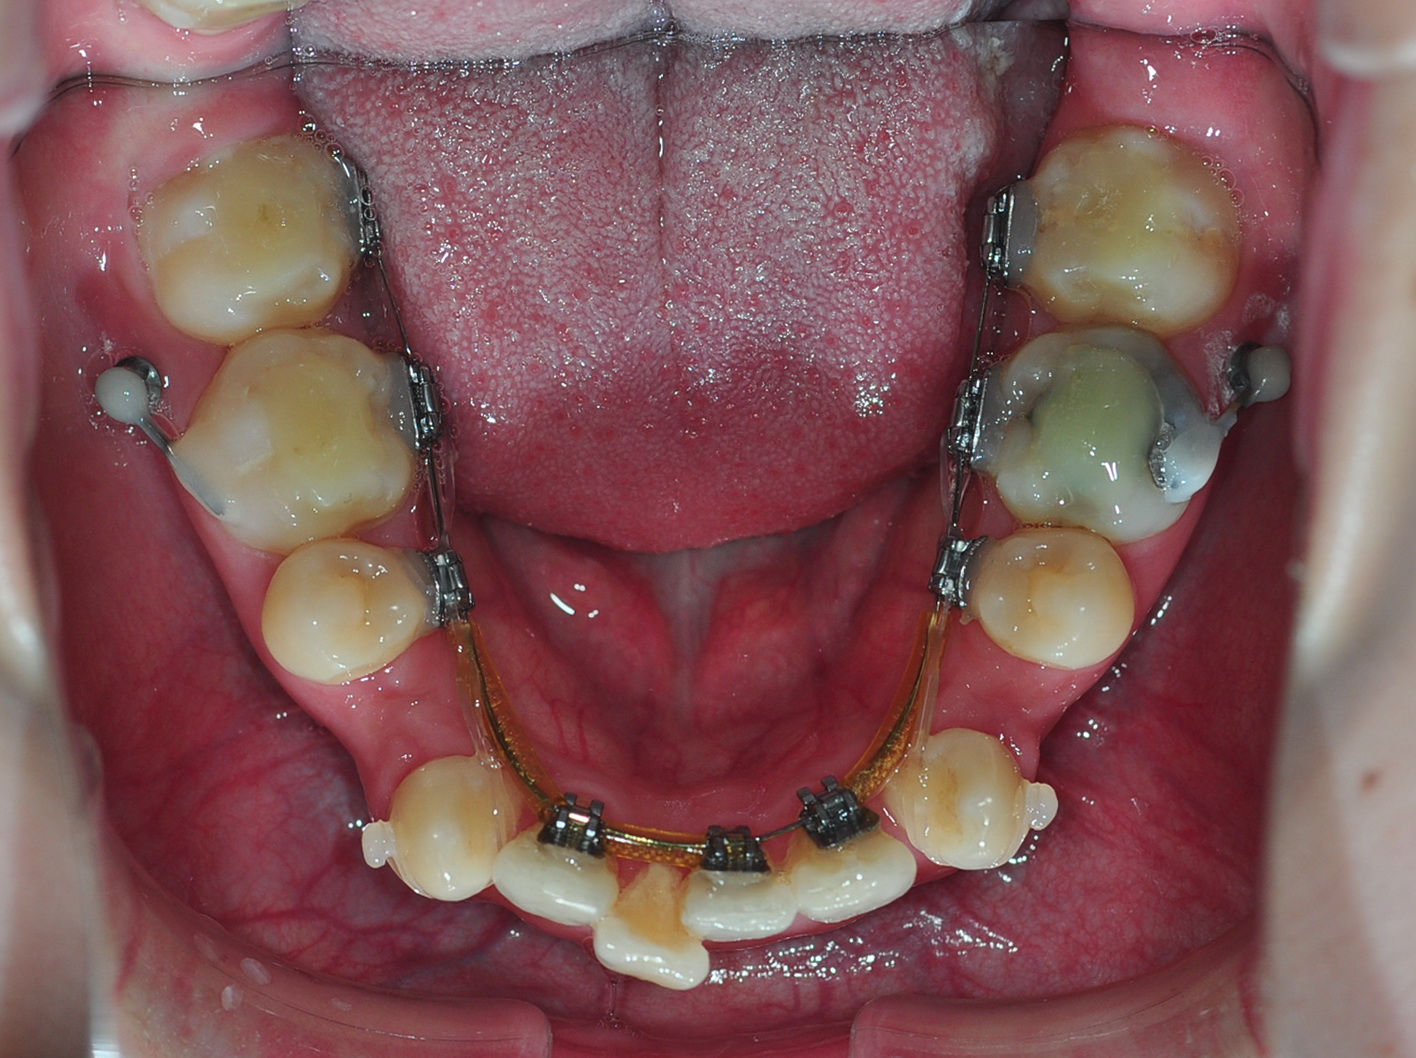

이번 월치료에는 상악에 고무줄 체인지,

하악에 어금니와 스크류 연결, 하악 송곳니에 고무줄을 감았답니다.

상악에 있는 스크류와 치아교정 장치를 연결하는 고무줄을

좀 더 강한 것으로 교체하였어용~~

그리고 하악 어금니 쪽에 있는 스크류에 동그란 것을 만들고

어금니와 철사로 연결을 하여주셨는데요

(음… 말이 좀 이해가 안되시죠 ㅠ.ㅠ 사진으로 확인해주셔용)

스크류는 지지대 역할을 하는 것이잖아요 ~

이것을 지지대로 하여 어금니와 연결함으로

어금니가 앞으로 당겨져 나가는 것을 방지하는 것이라고 하시더라구요~~

그리고 하악에 송곳니를 고무줄로 돌려서 치아교정 장치에 연결해주셨습니다.